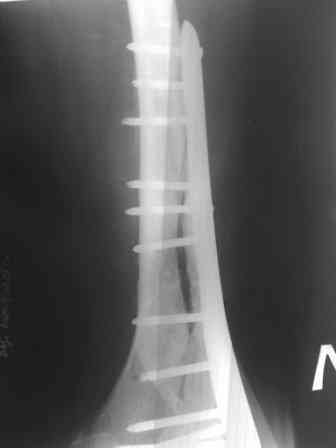

Спасибо большое, коллеги. Дополню. С момента травмы прошло 5 месяцев. Пластина

действительно блокированная. Пациент, конечно истощен, самостоятельно перемещаться не

может. Рана после ревизии 10х3см по краям гранулирует. На дне раны немного гнойного

отделяемого. фото раны представлю чуть позже. А пока добавляю боковую и 3\4 проекции.: